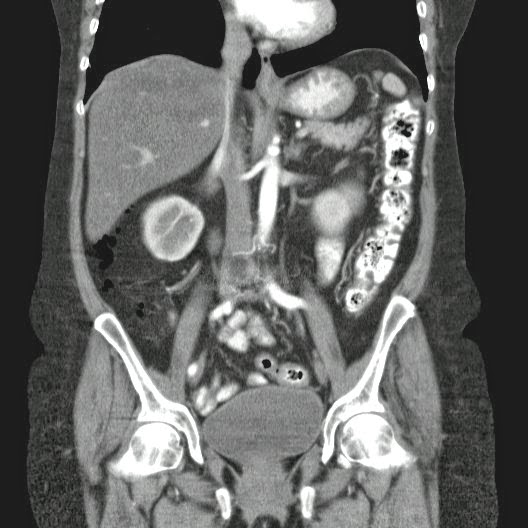

Caso Interesante #4

Adulto masculino, 1 semana de fiebre y malestar general.

¿Dónde esta ubicado el hallazgo?